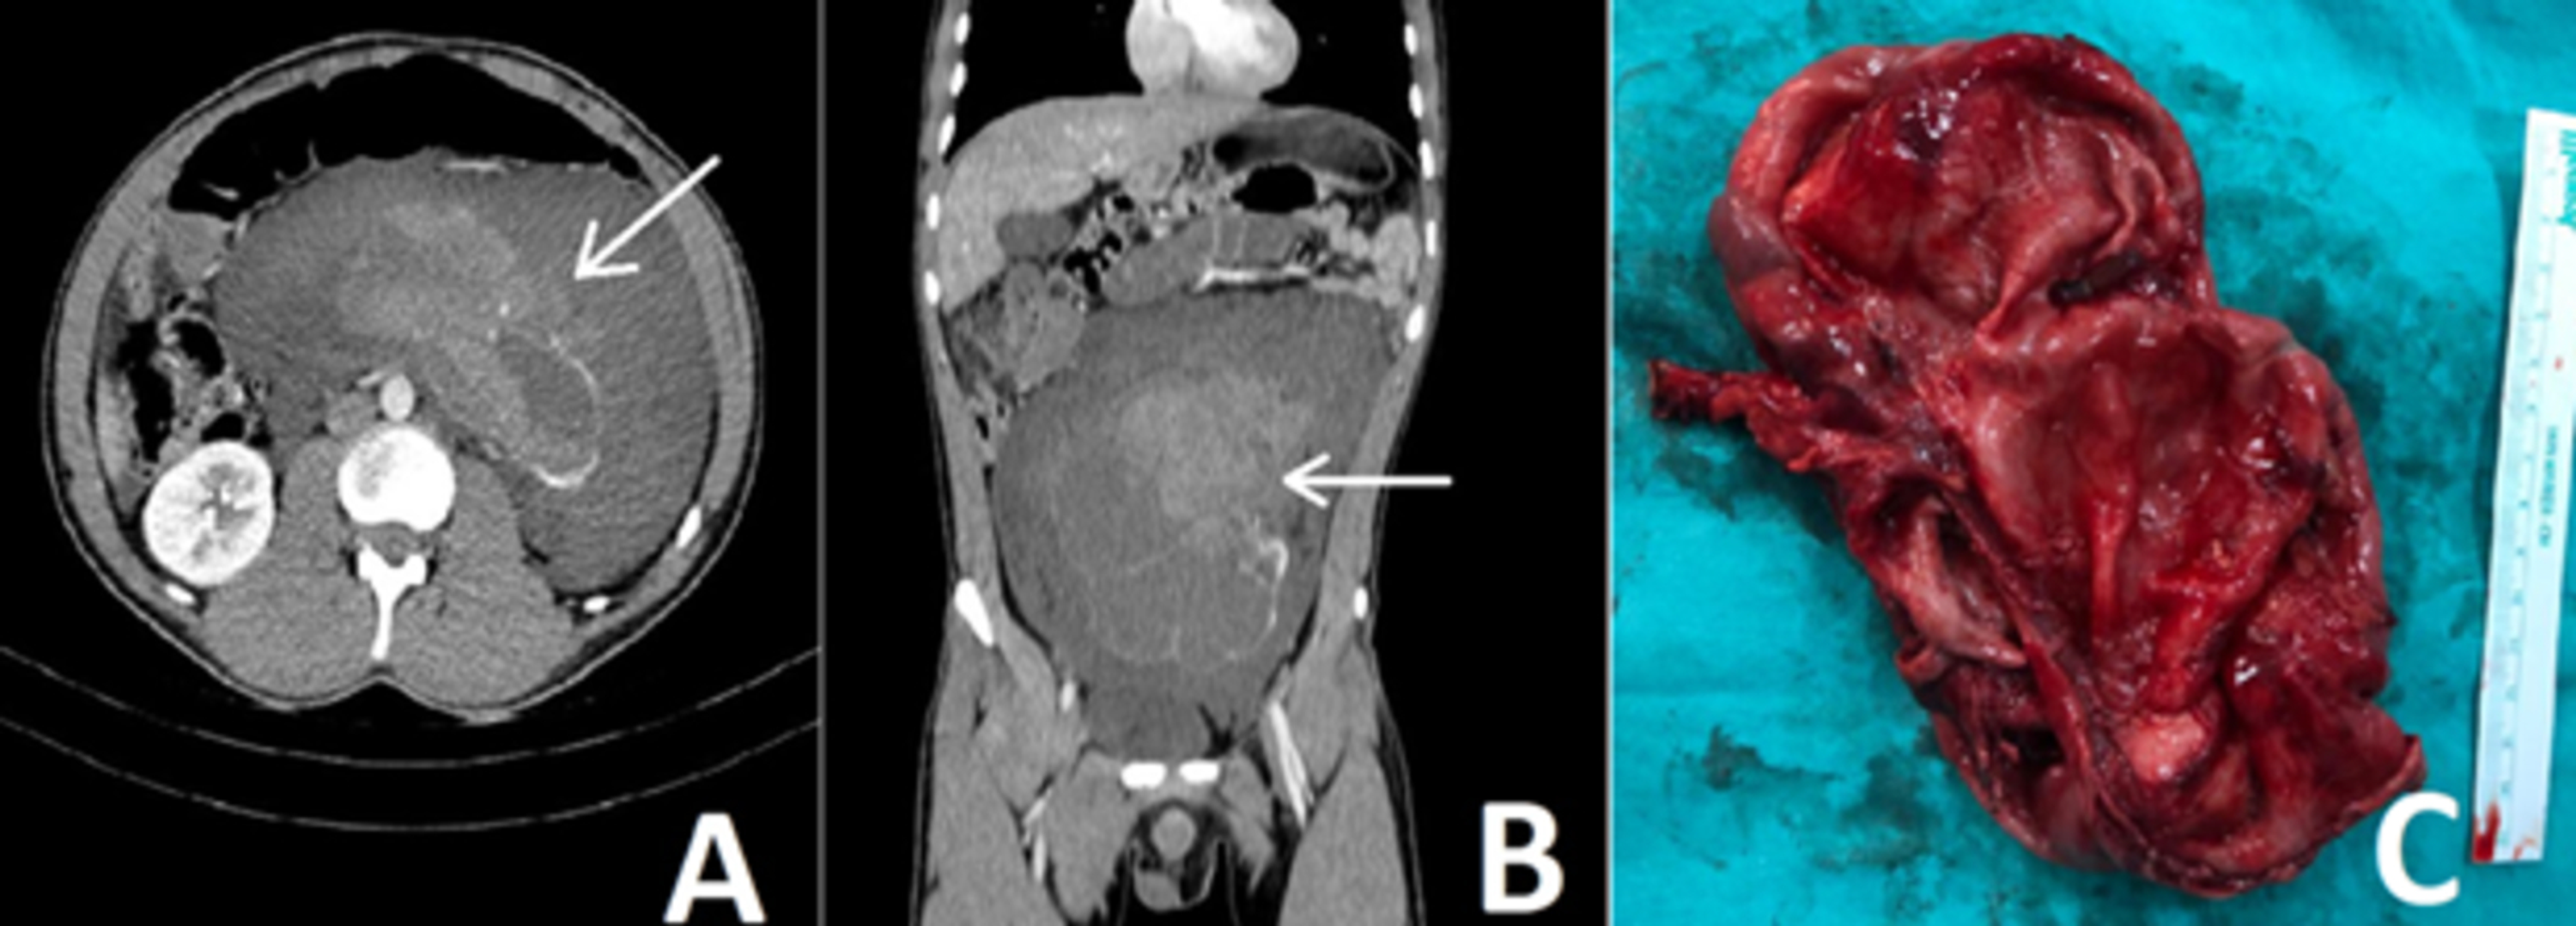

From www.annsaudimed.net

Spontaneous Rupture of the Kidney Case Report and Review of the Can A Ruptured Kidney Be Repaired Is time of the essence? The capacity to regenerate has mythic qualities for most of us, but the human body has. while a damaged kidney typically can’t repair itself, the condition can be treated if caught early. Acute kidney failure can be. Perspectives of the niddk (re)building a kidney consortium. treatment can be as simple as the placement. Can A Ruptured Kidney Be Repaired.

From www.cureus.com

Cureus Spontaneous Kidney Rupture Two Case Reports With Unusual Can A Ruptured Kidney Be Repaired treatment can be as simple as the placement of a stent into the ureter by a urologist, exploration and repair of the. while a damaged kidney typically can’t repair itself, the condition can be treated if caught early. Acute kidney failure can be. in most cases, kidney damage is permanent, but it may be possible to slow. Can A Ruptured Kidney Be Repaired.